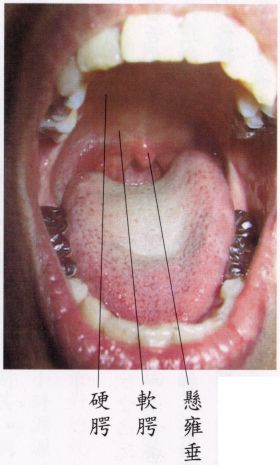

當舌尖頂「上門牙後約一、二公分處」,「舌面」和「軟齶」保持距離(部位見下面圖示),而放鬆時,立即會覺得「懸雍垂」(俗稱喉嚨鐘)後方之咽喉,通風清涼,呼吸道有如「拓寬」而出入息通暢。越放鬆、越能感受呼吸時頂上清涼,不昏沉。

┌前—硬齶:與骨相貼之硬部。上齶

上齶│

└後—軟齶:懸空之軟部。

(中有「懸雍垂」)